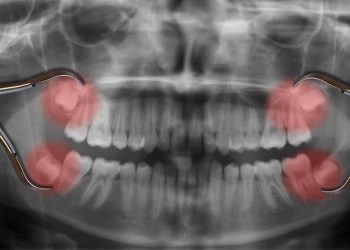

Signs You Need Your Wisdom Teeth Removed

Wisdom teeth, also known as third molars, are the last set of molars that most people get in their ...